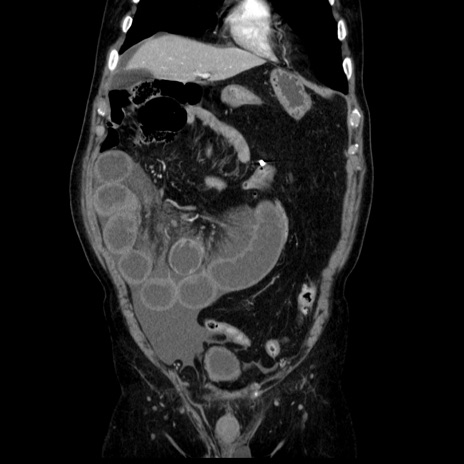

症例30(冠状断像)

【症例】80歳代男性

【主訴】臍周囲痛

【現病歴】約6時間前から臍下部痛が出現。次第に腹部膨隆・背部痛も生じてきたため来院。背部痛の場所は変化しない。

【身体所見】意識清明、BT 36.3℃、BP  131/87mmHg、P 87bpm、SpO2 100%(RA)、臍周囲自発痛・圧痛あり、反跳痛なし、自発痛部位に一致して板状硬あり、腹部膨隆、腸雑音減弱、CVA tenderness両側陰性。

【データ】WBC 19600、CRP 0.33